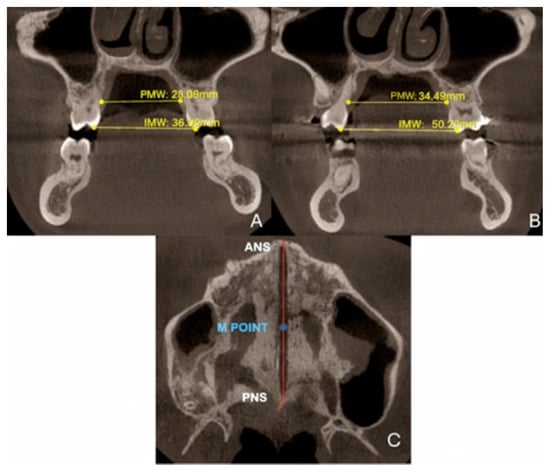

| Measurements | Pre-Treatment | Post-Treatment |

|---|---|---|

| PMW (mm) | 28.04 | 34.5 |

| IMW (mm) | 36.08 | 50.02 |

| SE (mm) | 0.32 | 7.82 |

| M16 (mm) | 0.6 | 0.7 |

| M15 (mm) | 1.6 | 2.3 |

| M25 (mm) | 0.7 | 1.3 |

| M26 (mm) | 1.2 | 0.9 |

| PAA 16 (°) | 93.6 | 96.2 |

| PAA 26 (°) | 109.6 | 112.2 |

| DTA 16 (°) | 89.06 | 91.6 |

| DTA 26 (°) | 100.9 | 102.9 |